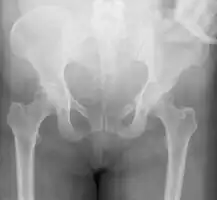

| A pelvic X-ray showing an open book fracture | |

Open book fracture

One specific kind of pelvic fracture is known as an 'open book' fracture. This is often the result from a heavy impact to the groin (pubis), a common motorcycling accident injury. In this kind of injury, the left and right halves of the pelvis are separated at front and rear, the front opening more than the rear, i.e. like an open book that falls to the ground and splits in the middle. Depending on the severity, this may require surgical reconstruction before rehabilitation.[10] Forces from an anterior or posterior direction, like head-on car accidents, usually cause external rotation of the hemipelvis, an “open-book” injury. Open fractures have increased risk of infection and hemorrhaging from vessel injury, leading to higher mortality.[11]